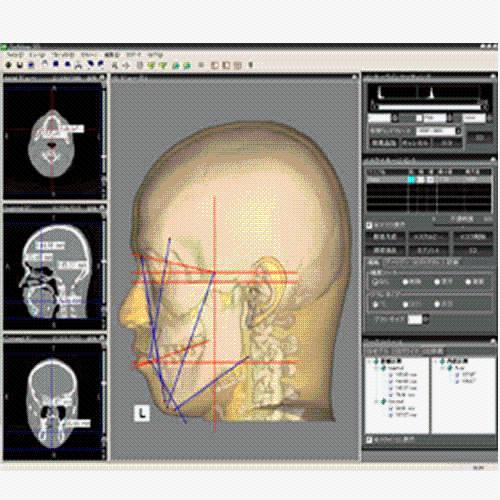

View X-Ray CT & MRI Scans Fast and Easily

FREE and easy to use 3D DICOM Viewer – for surgeons and patient education

Designed for surgeons, Pro Surgical 3D makes it easy to view patient scans quickly. Pro Surgical 3D facilitates the optimal 3D treatment and assessment workflows based on X-ray CT and MRI scans – and best of all, it’s FREE!

Traditional multi-planar slicing

High-quality and fast 3D reconstruction and 3D rendering

Multi-planar slicing.

Oblique slicing.

Instant and interactive surface extraction and export to STL and PLY formats.